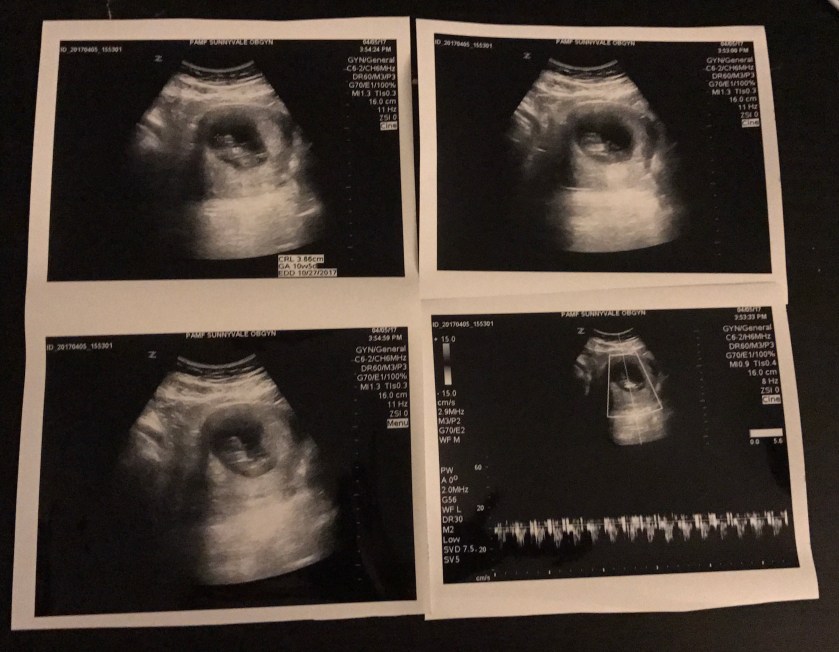

The highlight of my visits has always been the ultrasounds. The first two visits have had ones with the probe used internally, and I was delighted when the nurse told me this would be through my abdomen.

Our doctor told us they scan being external and with the fetal development would be less detailed than the others still we saw lots of great images including the one with the doctor’s finger pounding out our baby’s head that Matt took.

The doctor used the measuring tool to estimate me as 10 weeks 5 days pregnant with Estimated Due Date of October 27th.

The baby’s heartbeat was shown on the screen in colored lights and we got to hear the strong heartbeat as well. Of course we got many great sonogram pictures, even receiving and extra set for Candy.